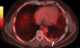

Pleural mesothelioma

Mesothelioma is a type of cancer that develops from the thin layer of tissue that covers many of the internal organs (known as the mesothelium). The most common area affected is the lining of the lungs and chest wall. [Source: Wikipedia ]